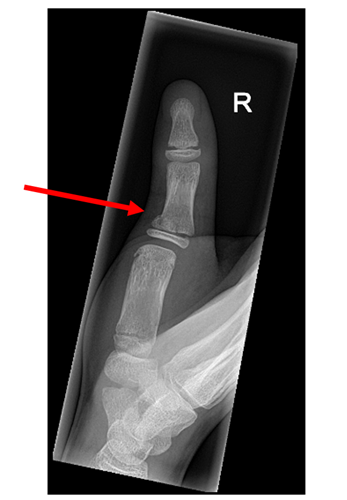

- AP and lateral views of specific individual fingers or the thumb should be requested